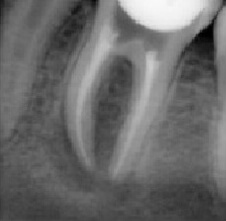

Проблема. Глубокая кариозная полость

Решение. Каналы были очищены, подготовлены к пломбированию, сделан дентальный снимок с пломбировочным материалом.

Запломбированы корневые каналы зуба. Зуб подготовлен к дальнейшему лечению.